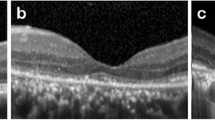

Four AO-TFI images were acquired in areas showing serous PED in the OCT sections of one eye with active CSCR (see supplementary Movie S7 online) and three eyes with resolved CSCR. Only one of these PED was not detectable in the BAF image (Fig. 4b). This persistent localized serous PED visible in the OCT section (Fig. 4d) appears as a hypo-reflective area in the IR fundus image (Fig. 4a). In the AO-TFI image, the PED is depicted as a distinct area composed of small, dense hyper-reflective dots, surrounded by a large bright border (Fig. 4c), which is typical of elevated photoreceptors in a singular pattern.

Pigment epithelial detachment (PED) in resolved CSCR (Left eye, Male, 46 years). (a) IR fundus area corresponding to the superior AO-TFI image shown in (c). The white line indicates the location of the corresponding OCT B-section (d). (b) Normal blue-autofluorescence fundus image indicating the approximated area imaged using AO-TFI (white lines) and the location of the magnified AO-TFI image (yellow square). (c, d) Correlation of the AO-TFI image with OCT B-scans showing PED. The vertical dot lines report the width of the distinct area sharply imaged with AO-TFI. The complete “IR fundus—AO-TFI—OCT B-scan” correlation is available in the supplementary Movie S5.